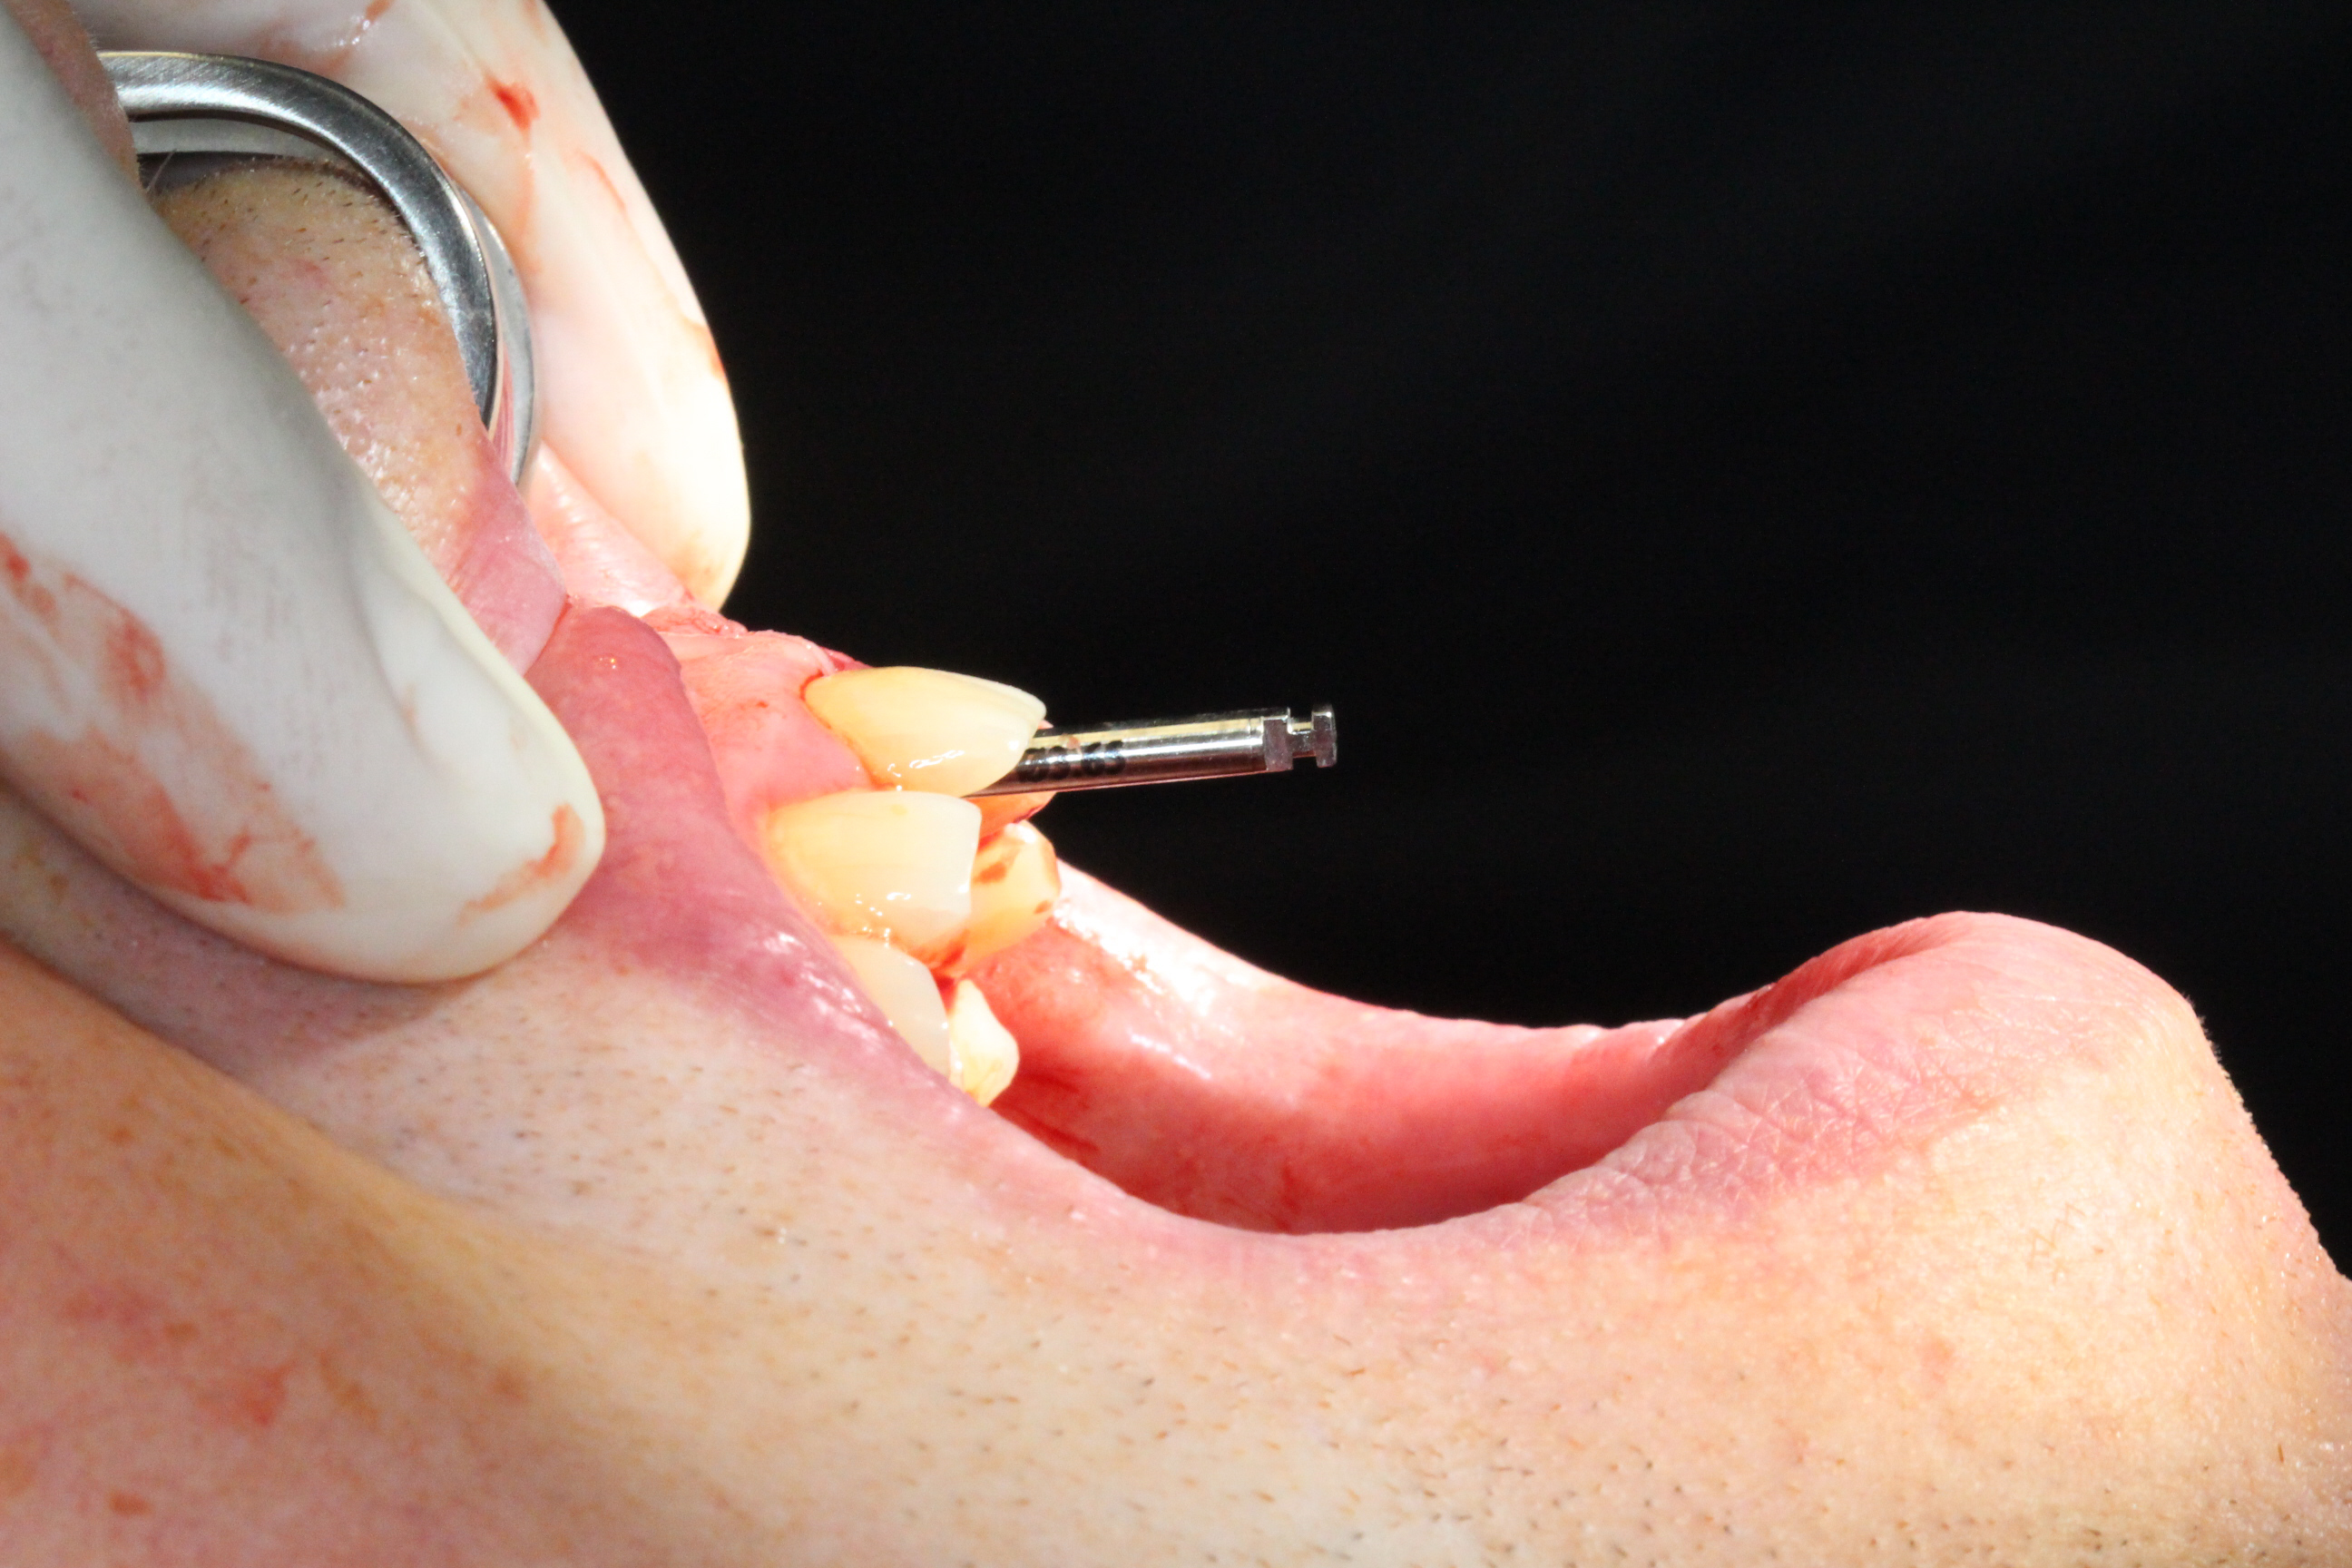

Immediate Loading

The prosthetic phase was performed by Dr. Simon Budak.

A Multi-Unit Abutment (MUA 1.6) was connected to the implant. Using a titanium sleeve, a temporary crown was fabricated chairside, and the implant was immediately loaded. Benefits of this approach included preservation of the extraction socket, maintenance of the interdental papilla, immediate restoration of aesthetics, and high patient satisfaction.

The patient left the clinic with a temporary crown on the day of surgery and was advised to follow a soft-food diet for the first month.